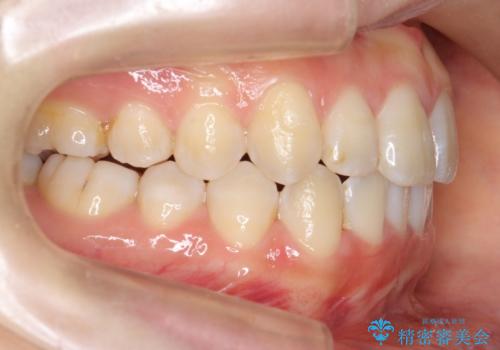

上下の前歯のがたつき 歯を抜かずに矯正

- 上下の前歯のがたつきを主訴に来院。

歯を抜かずに前歯を揃えています。

奥歯を後ろに下げたりなどはしていません。

奥歯を外に広げ、前歯中心に歯を少し削っていますが、健康には問題ない範囲で行なっています。